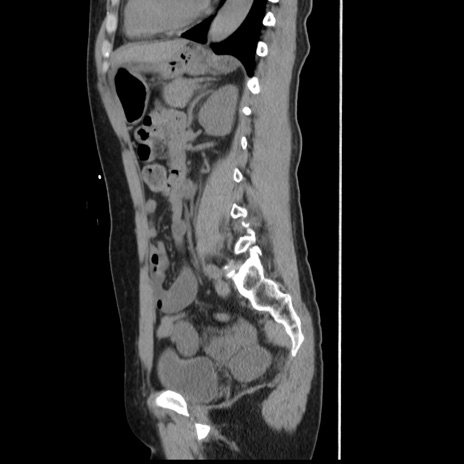

症例10(矢状断像)

【症例】 50歳代女性

【主訴】 腹痛

【現病歴】前日生レバーを食べた。今朝に排便あり。 昼前に突然発症の腹痛を生じ、当院救急外来を受診した。

【既往歴】 子宮筋腫にてで子宮全摘後

【身体所見】 意識清明、腹部:平坦、軟、下腹部やや左を中心に圧痛・反跳痛あり、筋性防御あり

【データ】WBC 7800、CRP 0.07